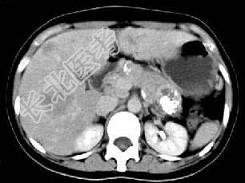

- 单项选择题根据所提供的图像,最可能的诊断为 ( )

A、胰尾囊腺癌肝转移

B、慢性胰腺炎

C、胰腺结核

D、胰岛细胞瘤

E、以上都不是